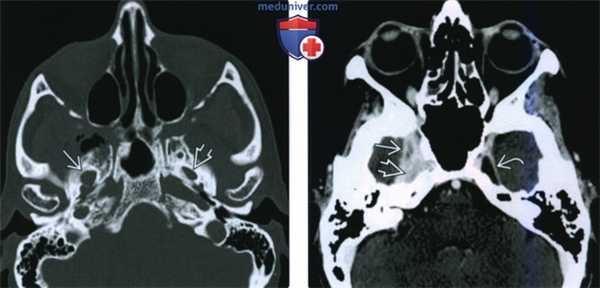

(Слева) Схема коронарной проекции, показана типичная злокачественная опухоль жевательного пространства, которая по волокнам нижнечелюстного нерва распространяется до овального отверстия и полости черепа.

(Справа) Пациент, у которого в анамнезе имеются сведения о пролеченном аде-нокисгозном раке щечного пространства. Онемение в области подбородка заставляет заподозрить рецидив опухоли и наличие периневральной инвазии. При МРТ Т1ВИ с КУ в коронарной проекции определяется опухоль, поражающая нижнечелюстной нерв в области жевательного пространства носоглотки. Опухоль проходит через овальное отверстие Я и начинает прорастать в тройничную полость. (Слева) МРТ Т1ВИ FS с КУ, аксиальная проекция, этот же пациент. Периневральное распространение опухоли в области нижнечелюстного отверстия. Обратите внимание, что с противоположной стороны накопление контраста минимальное. Однозначно, если рентгенолог целенаправленно не обращает внимание на этот признак, поставить правильный диагноз будет невозможно.

(Справа) МРТ Т1ВИ FS с КУ, аксиальная проекция, этот же пациент. Вокруг нижнечелюстного нерва, идущего в сторону овального отверстия, визуализируется опухолевая ткань, накапливающая контрастное вещество.